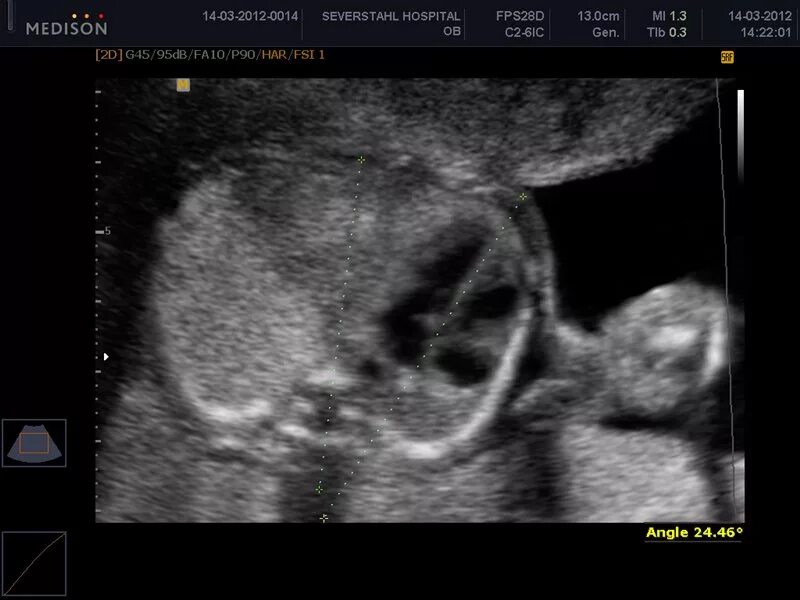

Узи аномалий